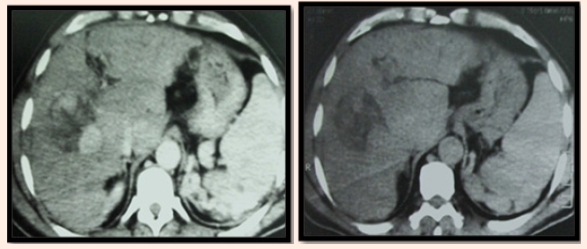

CT images after three weeks from RF ablation: Her CT showing partial about 50% ablation of the lesion with residual tumoral reactivity and no newly developed lesions. Then we decided to do TACE after 4weeks from RF ablation. She developed mild abdominal distension and minimal pelvic ascites that is controlled with drop of the AFP level to 46.6IU/DL. Follow up by Triphasic CT after 3months of combined therapy showing, Good uptake of lipiodol droplet by the residual tumoral tissue with no newly developed lesions. Follow up after three months of combined therapy was showing reduction of the size of the lesion into a hypo-dense non enhanced 3cm area with no residual tumoral reactivity and AFP reached 40 IU/DL (Figure 3).

Figure 3 CT Images after three weeks from RF ablation.

Follow up by triphasic CT after 3 months of combined therapy showing: Good uptake of lipiodol droplet by the residual tumoral tissue with no newly developed lesions. Follow up after three months of combined therapy was showing reduction of the size of the lesion into a hypo-dense non enhanced 3cm area with no residual tumoral reactivity and AFP reached 40IU/DL. After 6months patient developed mild ascites with mild elevation in AFP reaching 90IU/dl with deterioration of the liver function and CT showing no reactivity. After 8months of follow up she developed mild increased in AFP level reaching 110IU/DL then returning to 90IU/DL and a triphasic CT was done revealed no newly developed lesions or reactivity (Figure 4).

Figure 4 Follow up by Triphasic CT after 3 months of combined therapy.